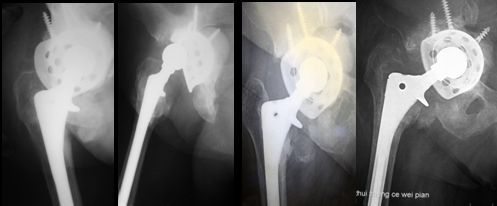

图7 第二次翻修取出的臼、柄、骨水泥块,肉芽肿组织

人的一生中人工髋关节可以翻修多少次?理论上,人工髋关节的翻修次数没有上限,目前已有不少第三次、第四次翻修成功的案例。但随着翻修次数的增加,手术的难度也不断增加,所以尽量减少翻修是人工关节置换技术努力的方向。